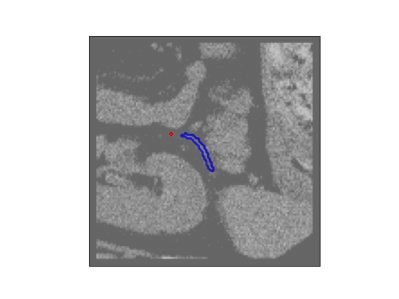

The human annotations are imperfect, especially when produced by junior practitioners. Multi-expert consensus is usually regarded as golden standard, while this annotation protocol is too expensive to implement in many real-world projects. In this study, we propose a method to refine human annotation, named Neural Annotation Refinement (NeAR). It is based on a learnable implicit function, which decodes a latent vector into represented shape. By integrating the appearance as an input of implicit functions, the appearance-aware NeAR fixes the annotation artefacts. Our method is demonstrated on the application of adrenal gland analysis. We first show that the NeAR can repair distorted golden standards on a public adrenal gland segmentation dataset. Besides, we develop a new Adrenal gLand ANalysis (ALAN) dataset with the proposed NeAR, where each case consists of a 3D shape of adrenal gland and its diagnosis label (normal vs. abnormal) assigned by experts. We show that models trained on the shapes repaired by the NeAR can diagnose adrenal glands better than the original ones. The ALAN dataset will be open-source, with 1,594 shapes for adrenal gland diagnosis, which serves as a new benchmark for medical shape analysis. Code and dataset are available at https://github.com/M3DV/NeAR.